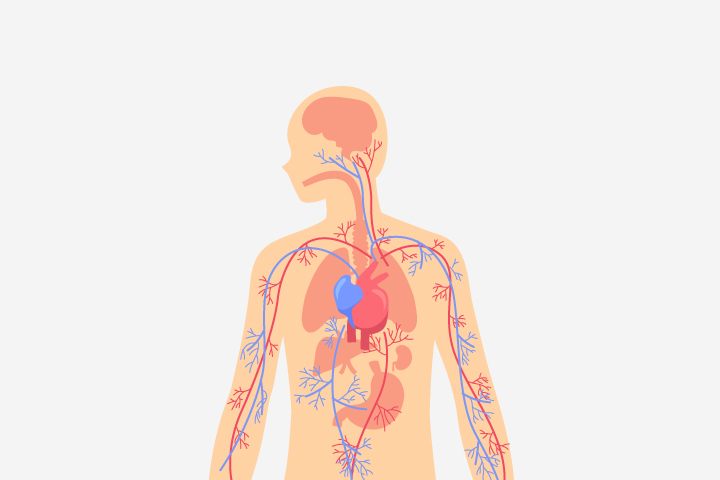

Sistem Peredaran Darah Manusia

Sistem peredaran darah manusia adalah berbagai fungsi untuk mengedarkan darah ke seluruh tubuh yang dilakukan melalui kerja sama berbagai organ yang memiliki tugas dan fungsinya masing-masing. Kita semua pasti telah mengetahui apa itu darah secara umum. Suatu ketika dalam beberapa kejadian yang tidak mengenakan mungkin kita pernah terjatuh dan sedikit terluka sehingga mengeluarkan darah.